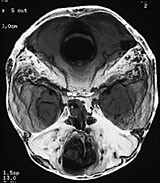

Cerebral CT med 3D-rekonstruksjon samt cerebral MR viste beindefekt mellom fremre skallegrop og mediale orbitavegg venstre side, samt en cystisk lesjon ca. 1,5 cm stor som dislokerte bulbus. Det var en stor og dyp utvidelse av fremre skallegrop. Normalt store ventrikler.